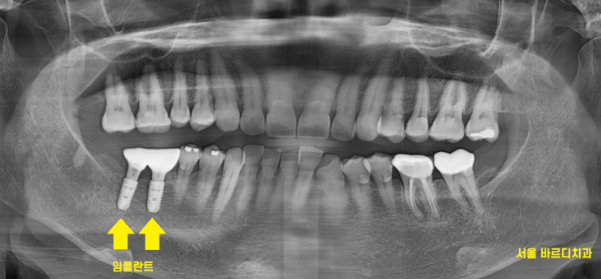

뼈 사진을 보시게 되면

임플란트 잘 심겨져 있답니다.

230817